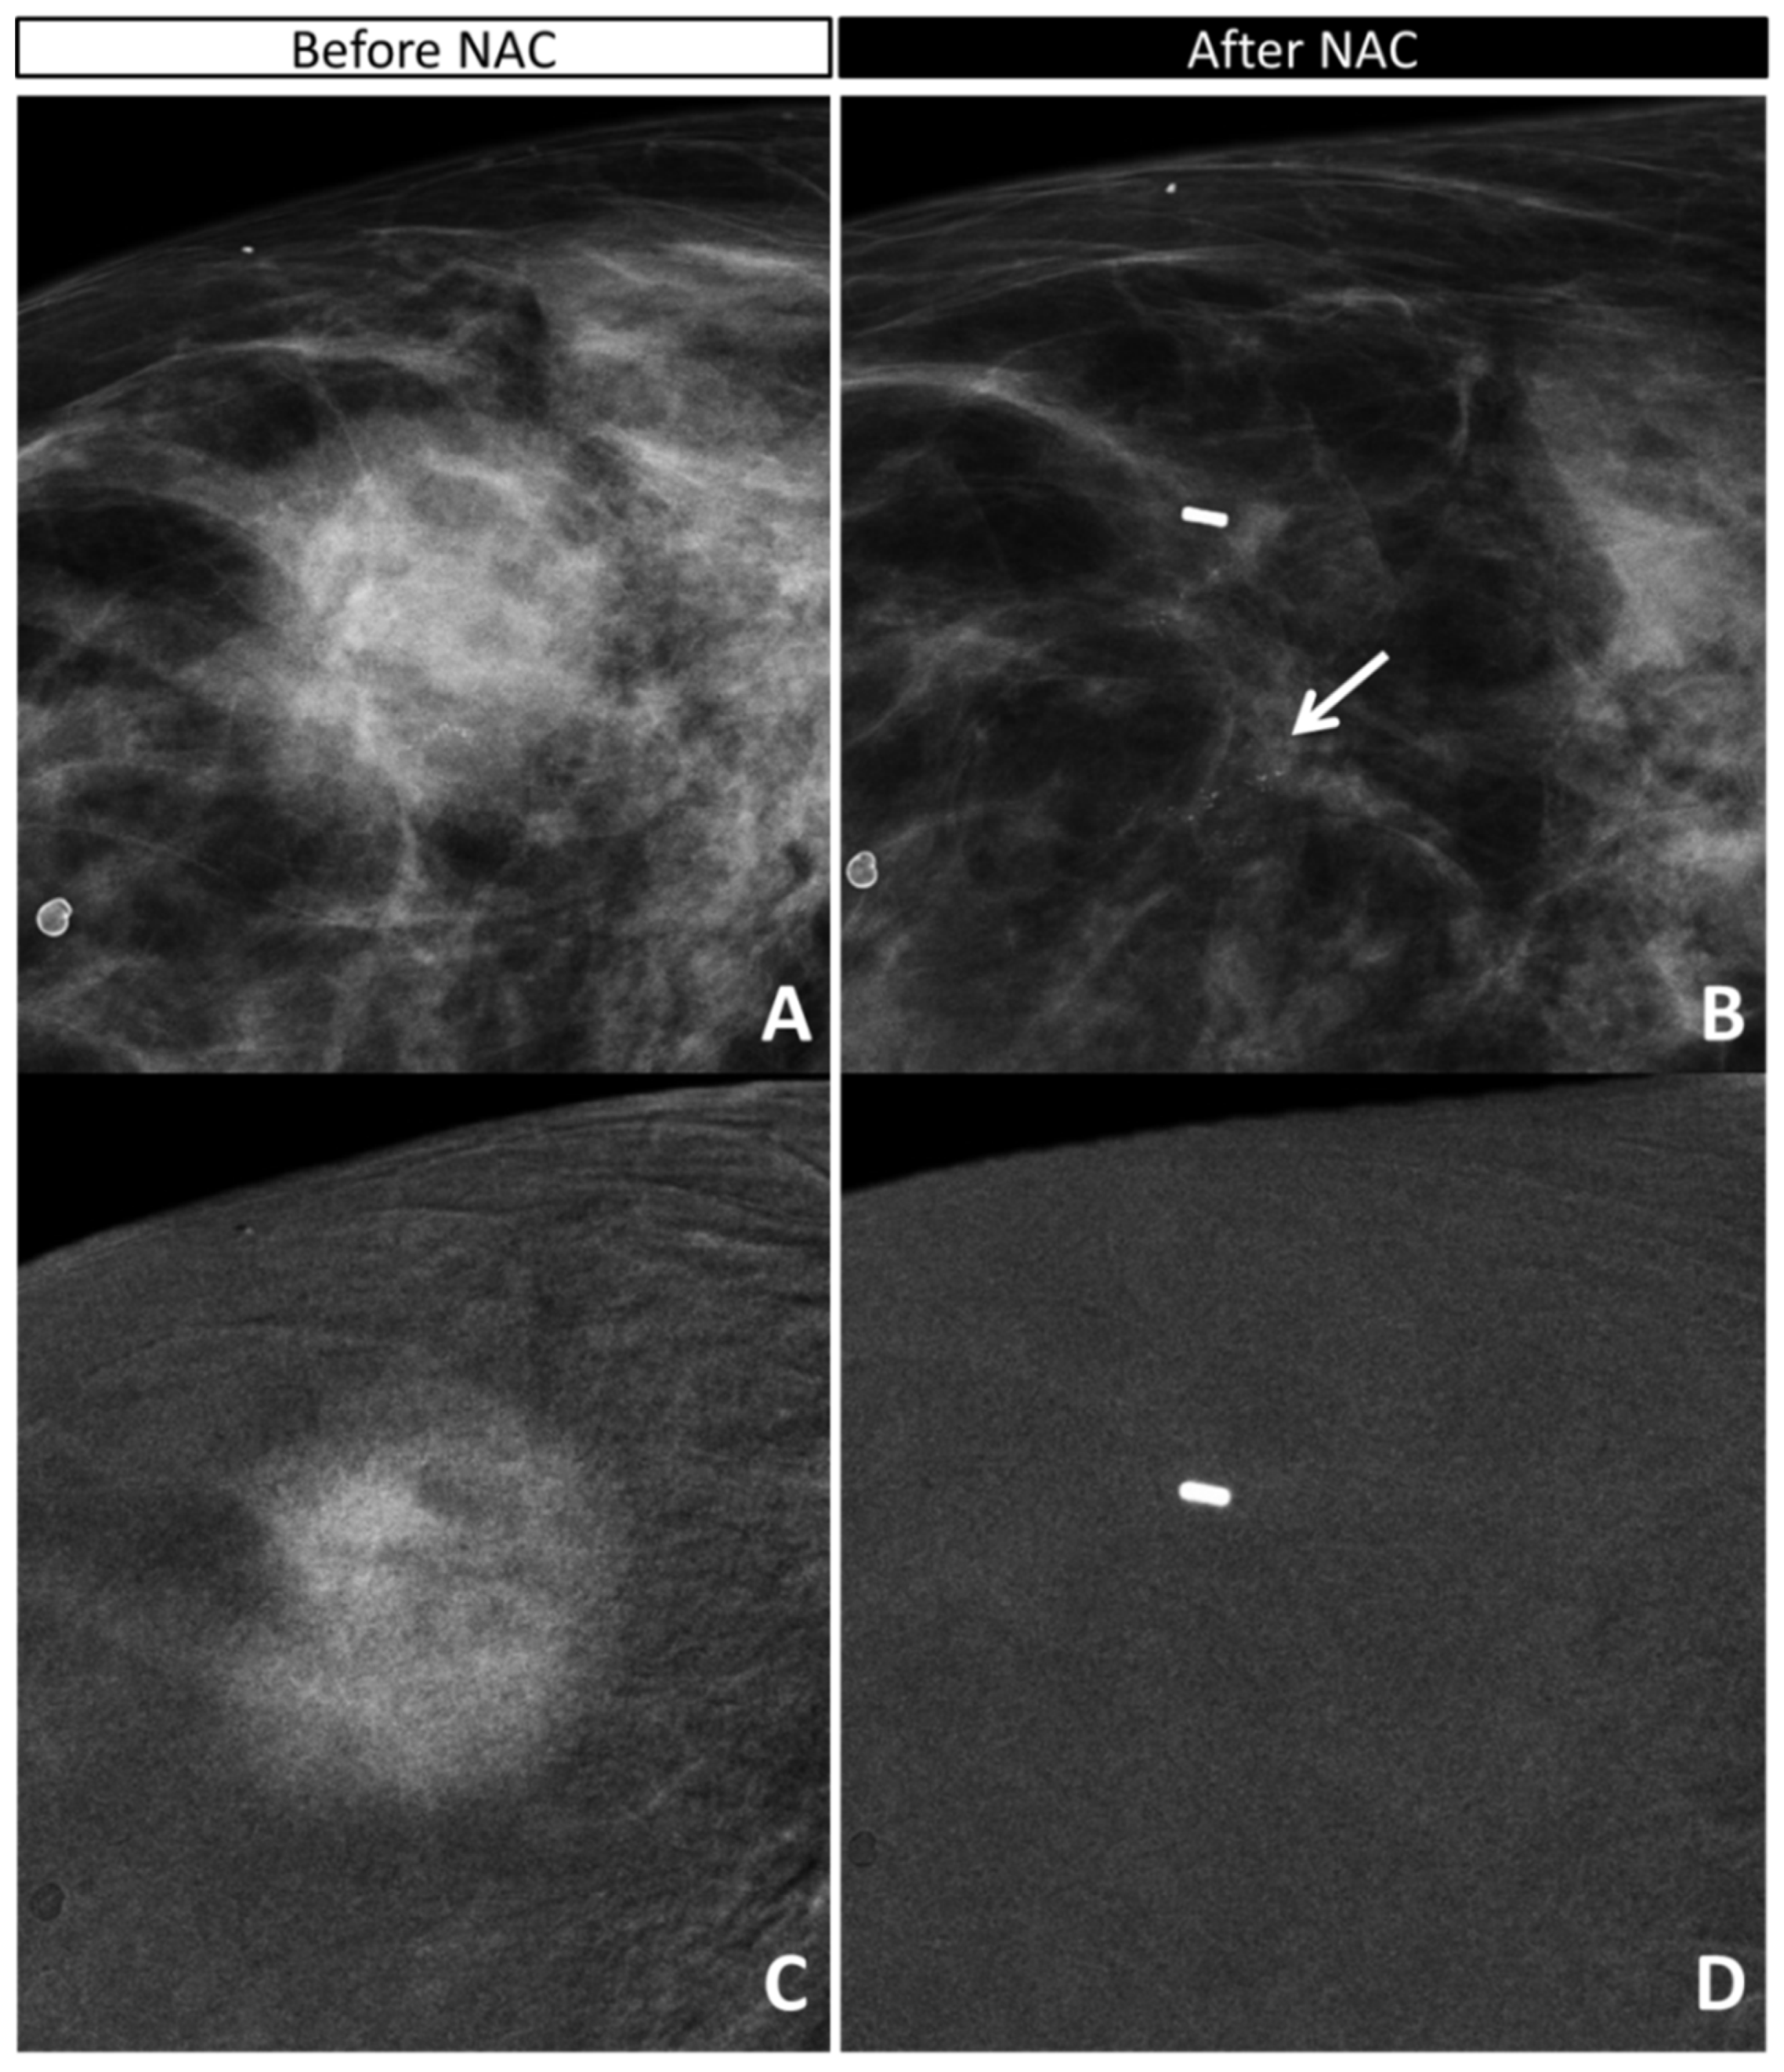

2.4. CEM Image Acquisition and Retrospective Review

- the absence or presence of contrast enhancement (CE) on recombined images, defining the maximum dimension (mm) of CE before NAC (defining the tumor bed) and after NAC (defining the residual disease);

- the maximum extension (mm) and characteristics (according to BIRADS lexicon) of calcifications on low-energy images before NAC (defining the tumor bed) and after NAC (defining the residual disease);

- the maximum extension (mm) of the combined evaluation of pathological calcifications and enhancement before (defining the tumor bed) and after (defining the residual disease) NAC;

3.3. Analysis of Discordant Cases

3.4. Concordance Between CEM and Pathology in the Measurement of Residual Tumor Size